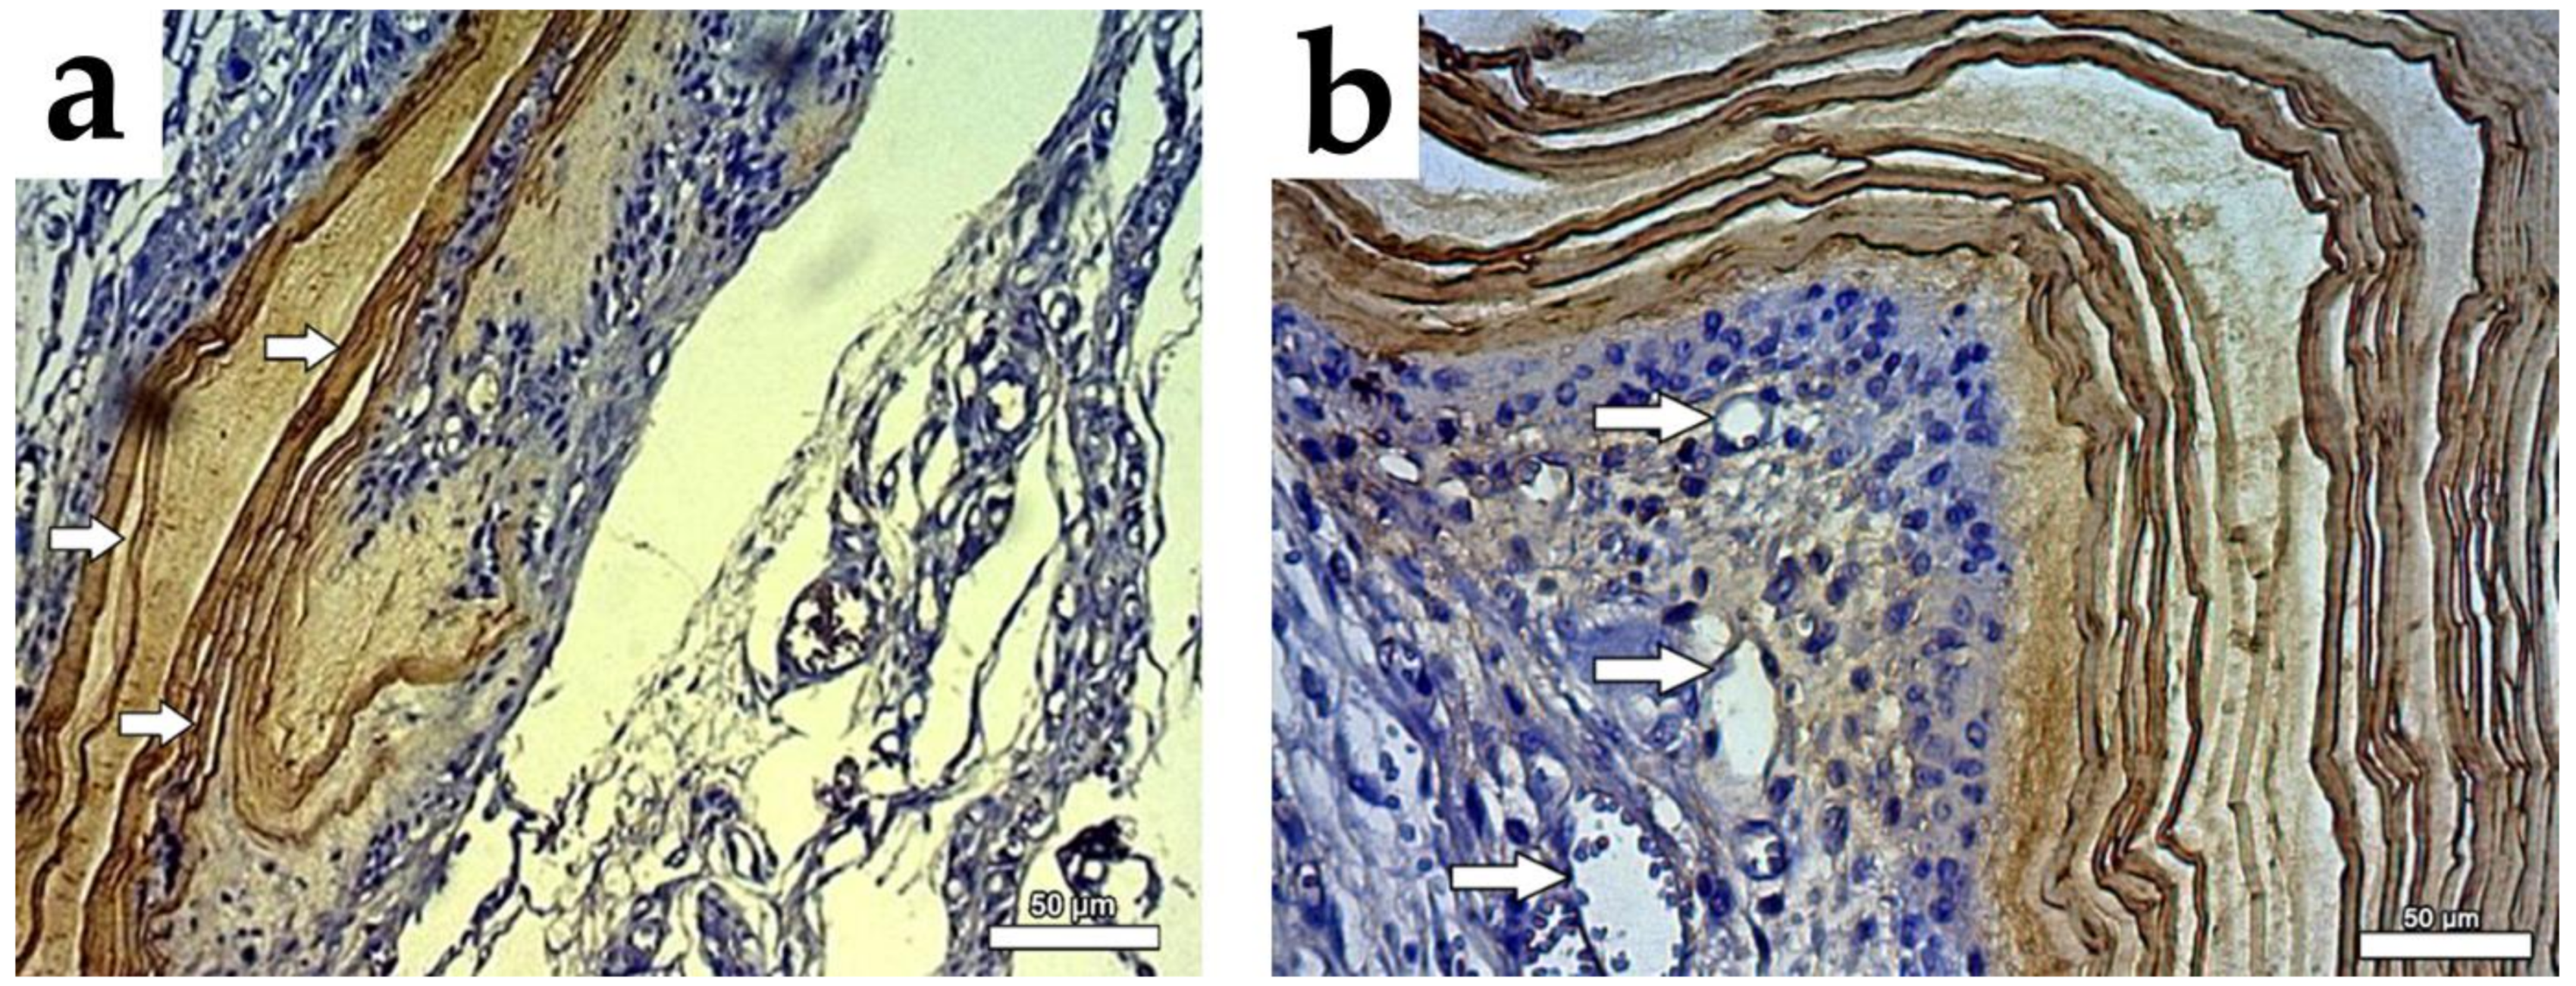

3.3. Histopathological Findings